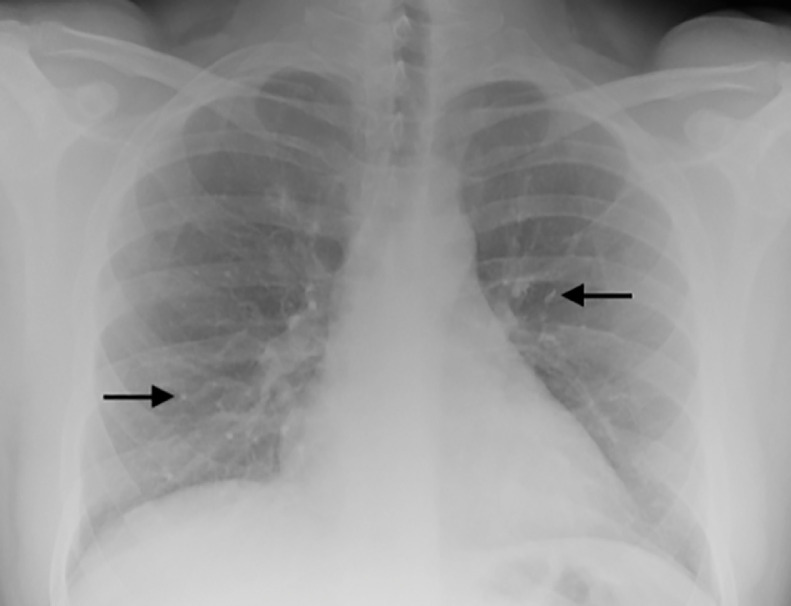

Fig. 1.

PA chest X-ray taken at time of patient's presentation. High attenuation foci, most notably within the right lower zone, were assumed to represent end-on vessels prior to the subsequent CTPA. Two example foci are highlighted by the black arrows.